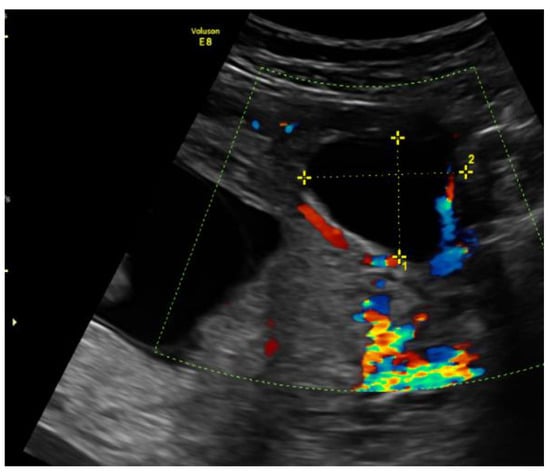

During hospitalization, blood and urine tests’ results were within the normal range. A multidisciplinary team (MDT) decided to keep monitoring the growth of both pregnancies by ultrasound while maternal vitals were stable and noted that further management would be determined according to the clinical situation. On the third day of hospitalization the patient started to feel more severe pain in the hypogastric region, radiating to the back and the left groin. The MDT made a decision to perform a diagnostic laparoscopy. Laparoscopy confirmed heterotopic angular pregnancy in the left enlarged, swollen cornu of the uterus. The left ovary and fallopian tube were not damaged and there were no signs of uterine rupture. Figure 3 and Figure 4.

Figure 5. Left cornu of the uterus visualized by transabdominal ultrasonography at the 22nd week of gestation.